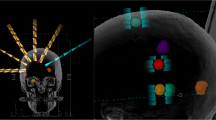

Figure 1 compares the beam arrangements and isodose distributions between the C-VMAT and HA-VMAT plans for patient #23, who had 3 metastases. In this case, the C-VMAT plan located the isocenter for each center of tumor (three isocenters) while HA-VMAT plan used only one isocenter. It can be observed that the HA-VMAT plan provides a steeper dose gradient for PTV (for all targets) and the resultant absolute volumes of the brain tissue receiving 10 (50% isodose) and 6 Gy (30% isodose) are 4.6 and 17.4 cc lower than the corresponding ones of the C-VMAT plan. On the other hand, the HA-VMAT plan resulted in a higher absolute volume of 16.8 cc when receiving a very low dose (V2Gy).